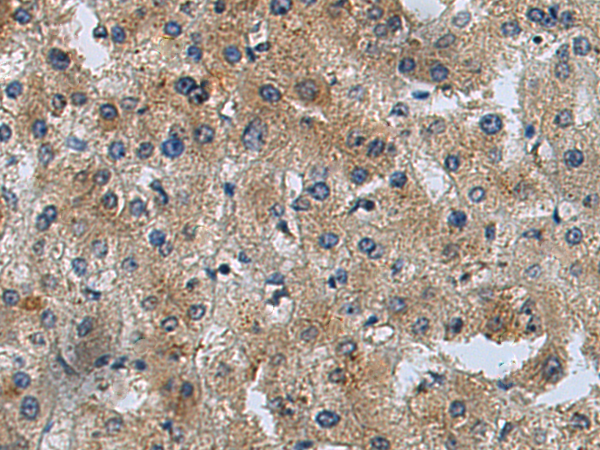

分类: 科研抗体货号: P02571别名: HVLP应用: WB,IHC反应种属: Human